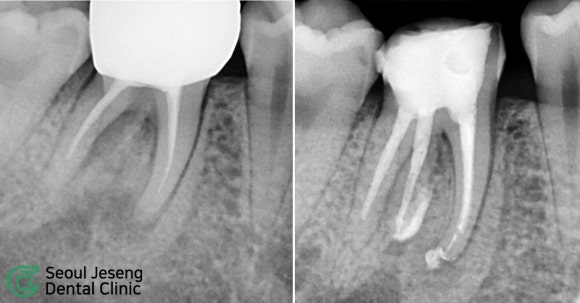

[치료사례] 재신경치료 (2)

#재신경치료 #미세현미경신경치료 #자연치아살리기 #치과보존과전문의 #신촌치과 #신촌서울재생치과